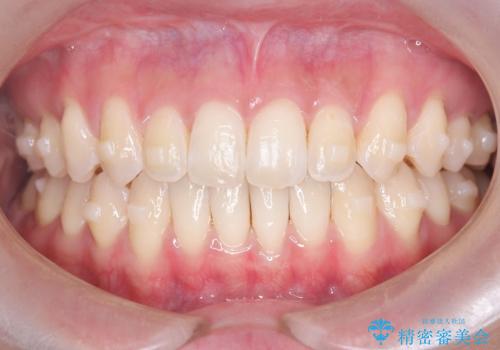

再矯正 前歯のガタツキをマウスピース矯正で治療したい

- 前に矯正治療をしたが、後戻りしてガタツキが出てきたので、治したいとのことで来院されました。

ワイヤー治療とマウスピース矯正、2通りの治療を提案させていただき、マウスピース矯正治療を希望されましたので、インビザラインによる治療を開始しました。

前歯のガタツキを改善する治療法として、マウスピース矯正が適していることが多いです。

マウスピース矯正は、金属製のブラケットやワイヤーを使用せずに、透明なマウスピースを装着して歯を移動させる方法です。そのため、目立たず、痛みも少ないです。